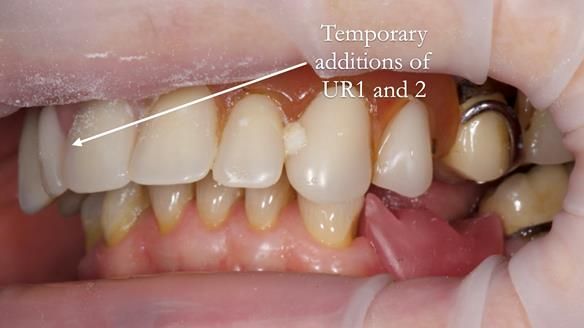

- The upper right central and lateral incisors with post crowns. Healthy and functionally secure but with poor appearance, contributing to the reverse curve.

- Add upper right lateral and central incisor denture teeth to existing upper RPD as temporary measure during making of new RPDs